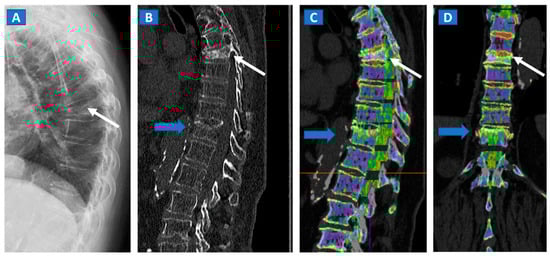

Figure 1.

An 82-year-old female, unable to undergo MRI, with non-traumatic dorsal vertebral compression fractures. On the sagittal standard radiograph (A) a mid-dorsal spine fracture can be seen (white arrow). On the high resolution sagittal 1 mm reconstructed CT image (B), an additional fracture of the D9 vertebral body is suspected (blue arrow). On the corresponding sagittal (C) and coronal DECT superimposed map (D), D5 and D9 fresh vertebral fractures are confirmed by the presence of BME, coded in shades of green (arrows), while normal bone is coded in violet.

In cases of bone sclerosis, which is relatively common amongst elderly individuals suffering from degenerative osteoarthritis, spared bone is typically coded in violet and BME in shades of green (Figure 1). As bone sclerosis can yield false positive findings [3,9], it is important to be aware of typical bone sclerosis sites so as to reduce the risk of misdiagnosis. It is also useful to compare symptomatic and asymptomatic sides, and to look for any asymmetry. Moreover, it is also recommended to progressively increase the threshold for BME and/or the level of superimposition of BME of bone window images, in order to obtain a clearer depiction. In selected cases, the quantitative assessment of DECT numbers, by using a ROI for questionable areas, can help to achieve a differential diagnosis. However, thresholds may vary widely depending on the anatomical area, age of the patient, and qualitative assessment of DECT images [3].

DECT can distinguish fresh from old vertebral compression fractures by demonstrating the presence of BME [11]. In a recent metanalysis evaluating 13 studies using MRI as reference for diagnosis, including 515 patients and 926 acute fractures, DECT overall sensitivity was 86.2% with a specificity of 91.2% and accuracy of 89.3% [18]. In addition, DECT can accurately determine the position of hardware inserted during spinal surgery, by reducing metallic artifacts. The high intrinsic contrast of DECT images also assists in determining a differential diagnosis, such as in cases of disc herniation (Figure 2).